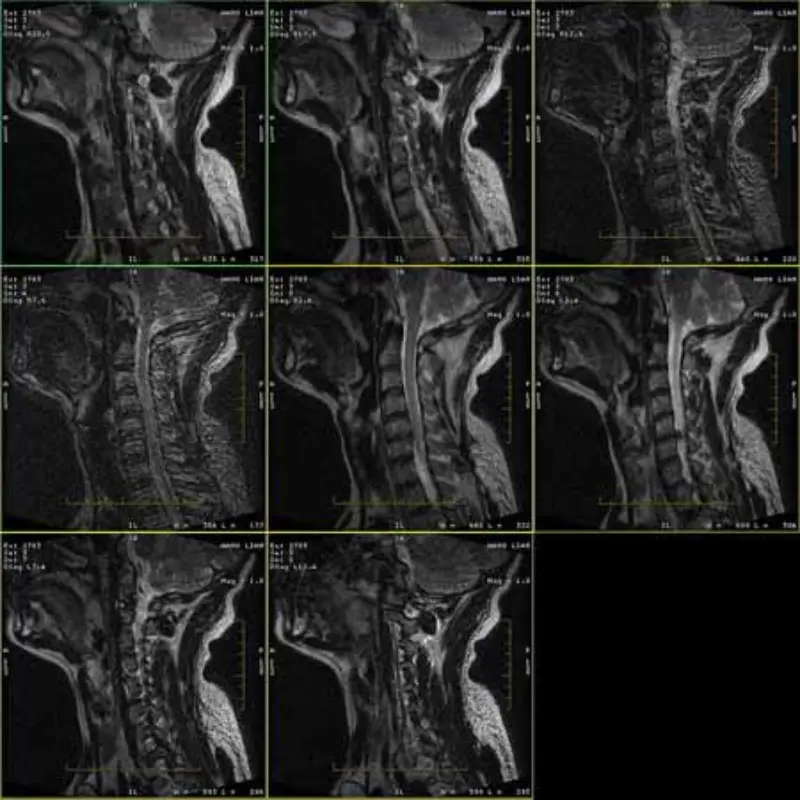

FRFSE এবং GRE প্রোটোকলের ছবিগুলিতে ভূত থাকে এবং কখনও কখনও কম SNR ছবিগুলি একটি সিরিজে প্রদর্শিত হয়। কিন্তু SE প্রোটোকল ইমেজ স্বাভাবিক.

ছবি সংযুক্ত দেখুন অনুগ্রহ করে.